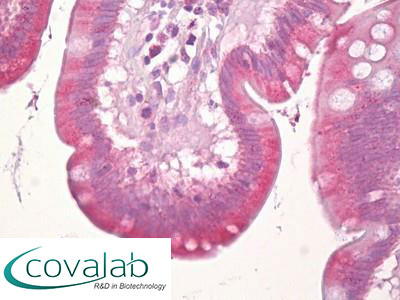

Anti-MARK3 antibody IHC staining of formalin-fixed, paraffin-embedded human small intestine after heat-induced antigen retrieval.

Anti-MARK3 antibody IHC staining of formalin-fixed, paraffin-embedded human small intestine after heat-induced antigen retrieval.